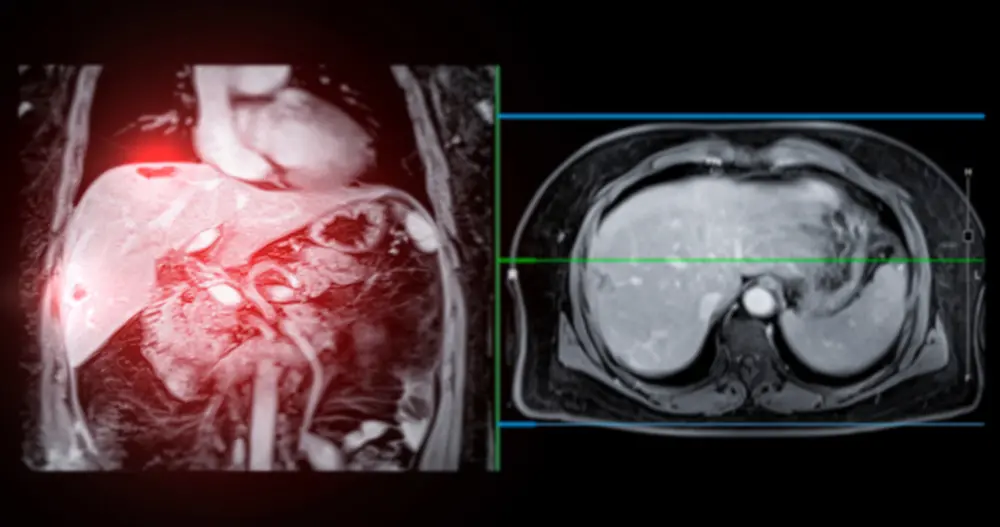

4-2. 정밀 검사

국가검진에서 이상 소견이 발견되면 추가 정밀 검사가 권장됩니다:

• 복부 CT (조영 증강)

• 복부 MRI

• 간 조직검사 (필요시)